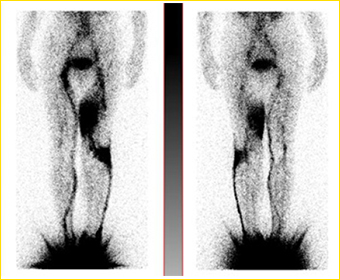

放射能をもつ薬剤(アイソトープ)を指の付け根などに注射し、リンパ管に取り込まれて流れる様子をシンチカメラという装置で撮影。流れている場所は筋状に、むくんでいる場所は雲のようにみえます。アイソトープには複数種あり、よく知られているのはフチン酸テクネシウム、ヒトアルブミンテクネシウムなどです。インドシアニングリーン検査と似ていますが、インドシアニングリーン検査は、狭い範囲を詳しくみることに適しており、リンパシンチグラフィーは全体の傾向をつかむのに適しています。一般的にアイソトープが筋状に見えるほど早期と診断されます。

(右)前面からの撮影。右足の流れは良好だが、左足内側のルートは消滅して、代わりに足の外側の流れが生じている。左足の膝の外側と内ももに浮腫が見られる。

(左)後面からの撮影。裏返しで観察できる。